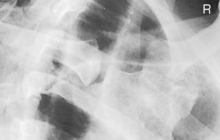

One suggested two-image routine is an AP or PA with the area of injury closest to the image receptor (IR) (above or below diaphragm) and an oblique projection of the axillary ribs on the side of injury. Therefore the oblique for this routine on an injury to the left anterior ribs would be an RAO shifting the spine away from the area of injury and to increase visibility of the left axillary ribs. The oblique for an injury to the right posterior ribs would be an RPO wherein the spine again is rotated away from the area of injury.

The location of the injury site in relationship to the diaphragm is important for all routines. Those injuries above the diaphragm require less exposure (nearer to a chest technique) when taken on inspiration and those below the diaphragm require an exposure nearer to that of an abdomen technique when taken on expiration.